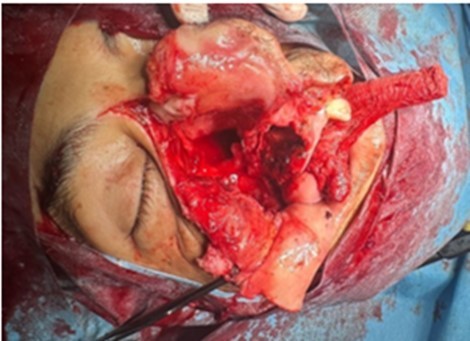

Patient aged 40 years without any surgical medical history who consults at our level in 2022 for a right epistaxis of average abundance with nasal obstruction and an induration next to the maxillary sinus right to palpation. Endoscopy revealed a reddish polypoid mass filling the right nasal cavity without palpable cervical adenopathies, CT returned in favor of an expansive tissue process of the right maxillary sinus, extended to the soft parts and the homolateral nasal cavity. The complete resection of the mass was performed by endonasal surgery (endoscopic maxilectomy). The histological examination found hemangioendothelioma without signs of malignancy with infiltrated margins, external complementary radiotherapy was indicated (50 Gy, 2Gy per day for 5 days a week on the maxillary sinus), a radiological check (MRI) 4 months later does not find any residual tumor. After an absence of 15 months, the patient revisits for resumption of symptomatology with right epistaxis of great abundance requiring 2 globular units, a reddish mass protruding from the nasal vestibule, lysing the bony palate with extension towards the cheek (Figure 1) and alteration of the CT and MRI find an expansive tumor process centered on the nasal cavity and maxillary sinus right of 103x 58 x41 vs 156x67x95mm with currently highly elevated spans, the process is globally hypodense and weakly elevated, presence of some vessels as well as hypervascular portions of peripheral localization at the extended jugal level and in front of the internal canthus, bone palace lysis, with a negative extension balance (Figure 2).

Figure 1.Clinical presentation of the patient objectifying the nasal and palatal jugal involvement.